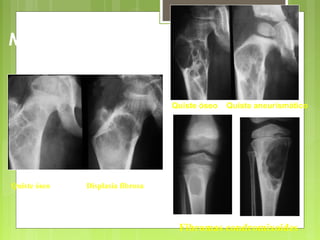

Quiste óseo Quiste aneurismático

Quiste óseo Displasia fibrosa

Condroblastomas Tumor a células gigantes Quistes aneurismáticos

Epífisis

Fibromas condromixoides

Metáfisis